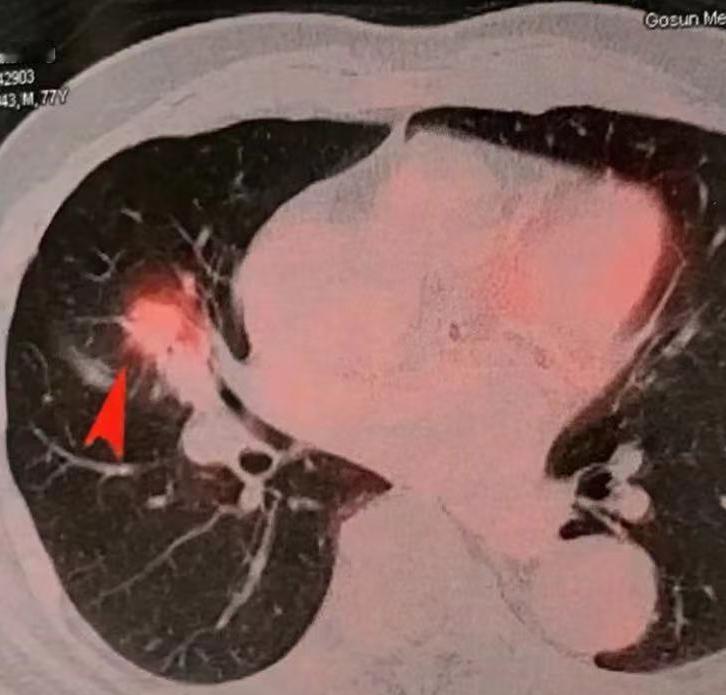

肺癌的免疫治疗,很多晚期病人用上之后,效果非常明显,甚至能实现长期生存。那不少早期患者也会来问:“既然免疫治疗这么好,我们能不能也用上?” 其实,免疫治疗的原理并不复杂。我们的身体本身就有免疫系统,就像一套防御机制,能识别和清除外来的病毒、细菌,也包括体内产生的异常细胞,比如肿瘤细胞。但肿瘤很“狡猾”,在生长过程中,它会伪装自己,逃避免疫系统的攻击——这就像给免疫细胞“蒙上了眼睛”。 而免疫药物,比如PD-1/PD-L1抑制剂,作用就是撕掉这层伪装,让免疫细胞重新识别并攻击肿瘤。 过去,科学家也尝试过不少免疫疗法,比如把别人的免疫细胞输给患者,或者用药物刺激免疫系统增强反应,但效果都不理想。直到这类“免疫检查点抑制剂”问世,才真正改变了晚期肺癌的治疗格局。 那么问题来了:早期肺癌患者需要免疫治疗吗? 目前来看,大部分早期肺癌患者,单纯通过手术切除就可以达到很好的治疗效果。因为肿瘤没有扩散,切除后复发风险低,这时候再加免疫治疗,并没有明确的必要。 不过,对于一部分中期或局部晚期的患者,情况就不一样了。最近一项覆盖全球一千多例患者的研究显示,这类患者在手术后配合免疫治疗,效果非常显著: 复发和转移的时间明显推迟;总体生存时间也大幅提升。 具体数据上,如果术后不用免疫治疗,五年生存率大概在70%左右;而加用了免疫治疗之后,可以提高到80%左右。也就是说,对于肿瘤负荷较重、复发风险较高的非早期患者,术后辅助免疫治疗确实能带来实实在在的生存获益。 所以总结来说:免疫治疗虽好,但也要看分期。早期患者通常手术就够了;而对于中期或局部晚期的患者,如果配不上靶向药,术后加用免疫治疗,已经成为提高治愈机会的重要策略。[玫瑰][谢谢]